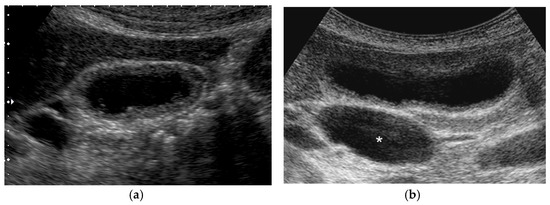

Figure 7. Cystic structures (anechoic spots) corresponding to RAS. Compared to the conventional US (a), CEUS clearly depicted cystic structures inside the fundal ADM (b).

CEUS can detect RAS better than conventional US, because RAS remains anechoic while the GB wall is enhanced (Figure 7). Tang et al. [35] reported that a small non-enhancement space observed in both arterial and venous phases was a characteristic finding of ADM, and CEUS (100%) could increase the degree of visualization of RAS compared with conventional US (67%). Yuan et al. [36] reported that intramural anechoic space was detected in 56.1% of focal ADM in contrast to 20.6% of GBC (p = 0.002).